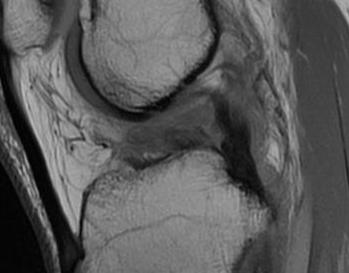

Sagittal MRI demonstrating patella tendon avulsion and ACL / PCL tear